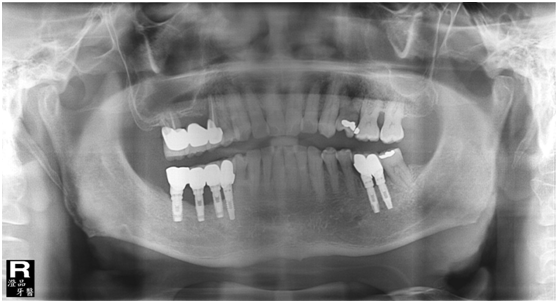

患者的原始片 91/06/13

患者陳先生於91/06/03初診,為一個牙周病患者,合併有右下缺牙。經過保守性牙周處理後,於91/08/14放置右下三顆植體。

完成後大約半年至一年進行一次例行性追蹤檢查,並無特別問題。以下為96/08/13時的追蹤小片,可以見到當時三顆植體的骨高度並無顯著變化。但右下第一小臼齒此時發現有搖動度增加的情形,當時對該顆牙做了咬合調整,降低咬合功能負荷,希望能有所改善。

96/08/13